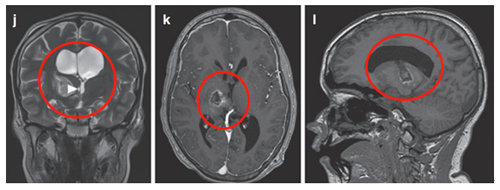

术后MRI显示囊性占位接触,脑室慢慢恢复正常。(图5j)四个月后,由于患儿的偏瘫没有改善,Rutka教授为其行经胼胝体半球间入路及肿瘤次全切除术。

术后影像(图5),术后患儿偏瘫改善,患儿生长和智力发育正常,近期随访显示脑瘤未复发。免疫组化检测RAFV600E突变免疫无阳性,H3K27M阴性。

(图5)